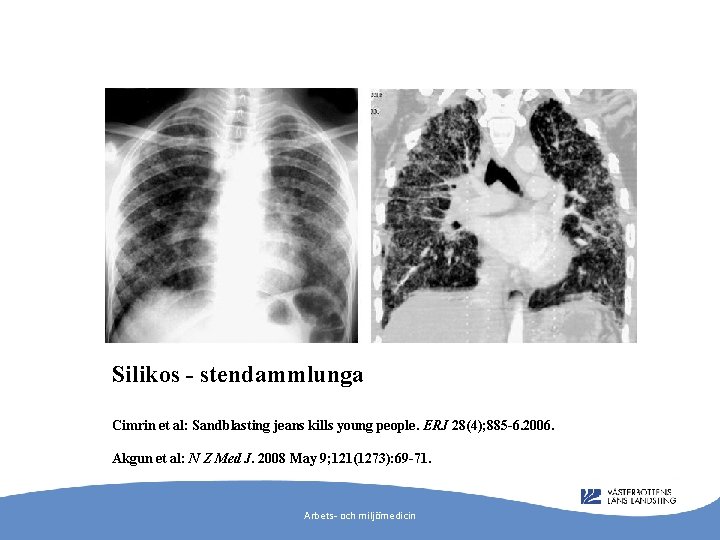

”A 17 -year-old man presented to hospital with dry cough and pleuritic chest pain. For approximately 2 years he had worked in a textile factory as a denim sandblaster using silica-containing sand to abrade denim material. ” Arbets- och miljömedicin

Silikos - stendammlunga Cimrin et al: Sandblasting jeans kills young people. ERJ 28(4); 885 -6. 2006. Akgun et al: N Z Med J. 2008 May 9; 121(1273): 69 -71. Arbets- och miljömedicin